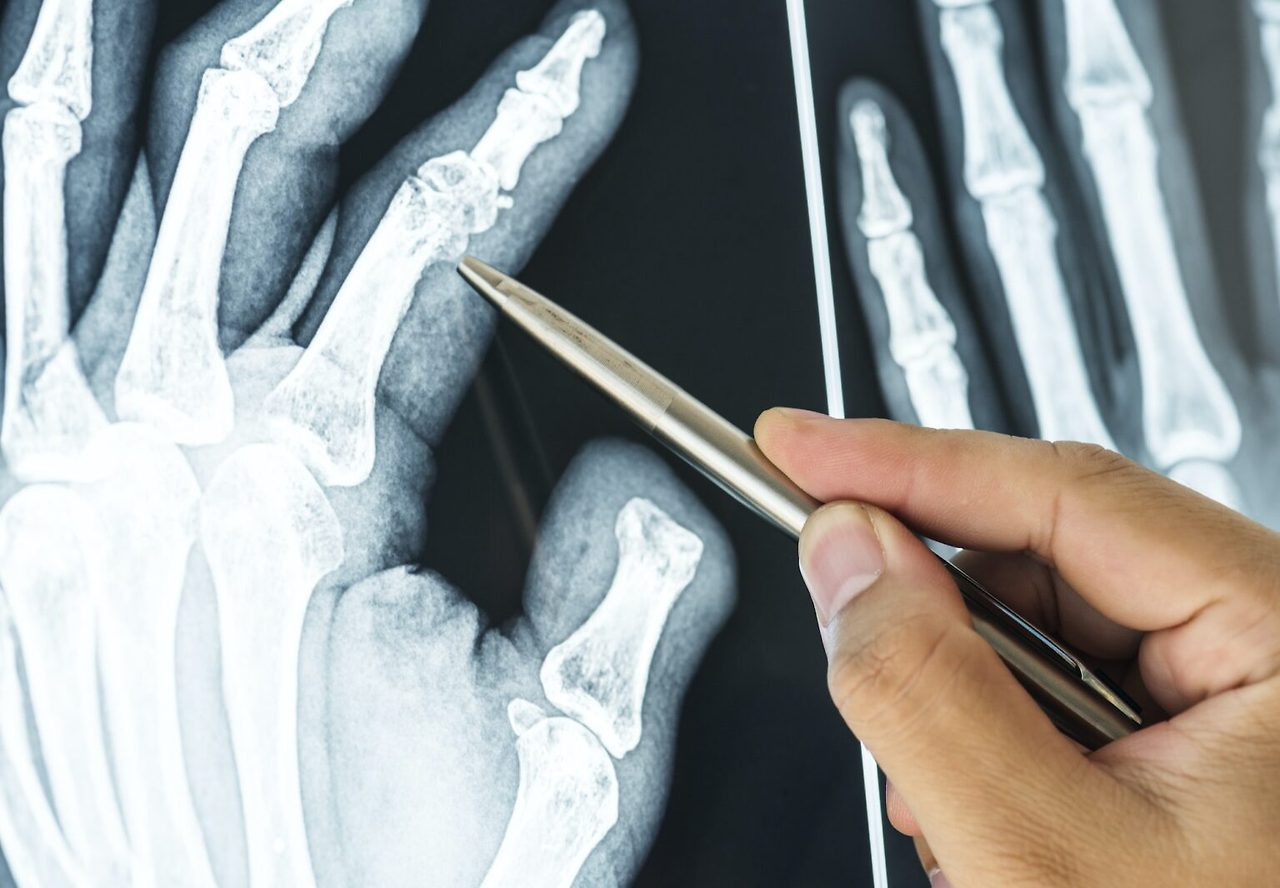

발가락 골절 완치기간, 엄지‧새끼손가락 뼈에 금이 가면? 깁스, 스플린트

발가락이나 손가락 뼈 골절은 일상에서 예상치 못하게 자주 발생하는 부상 중 하나입니다. 가구 모서리에 발가락을 찧거나, 축구를 하다가 발등을 세게 차이거나, 손가락으로 무거운 물건을 받치는 과정에서 순식간에 뼈에 금이 갈 수도 있습니다. 특히 발가락은 우리의 체중을 지탱하는 데 큰 역할을 하고, 손가락은 섬세한 작업에 필수적이므로, 골절 시에는 일상생활 전반이 불편해집니다.

하지만 “부러진 뼈도 언젠가는 붙겠지” 하며 막연히 방치하기보다는, 적절한 치료와 재활 과정을 거쳐야 빠르고 건강하게 회복할 수 있습니다. 본 포스팅에서는 발가락 골절과 손가락 뼈에 금이 갔을 때 손가락 골절 완치기간과, 엄지발가락 뼈에 금이 가면 발가락 완치기간, 그리고 깁스나 스플린트 사용법 및 수술 여부 등 다양한 정보를 자세히 살펴보겠습니다.

발가락 골절이란?

발가락 골절은 말 그대로 발가락 뼈(지골)에 금이 가거나 완전히 부러지는 상황을 뜻합니다. 일상 속 작은 충격부터, 스포츠 활동 중 강한 타격까지 다양한 원인으로 생길 수 있습니다. 특히 발가락 끝이 가구에 부딪히는 사소한 실수로도 골절이 발생할 수 있어, “정말 작게 다쳤는데 의외로 크게 아프다”라는 말을 자주 듣게 됩니다.